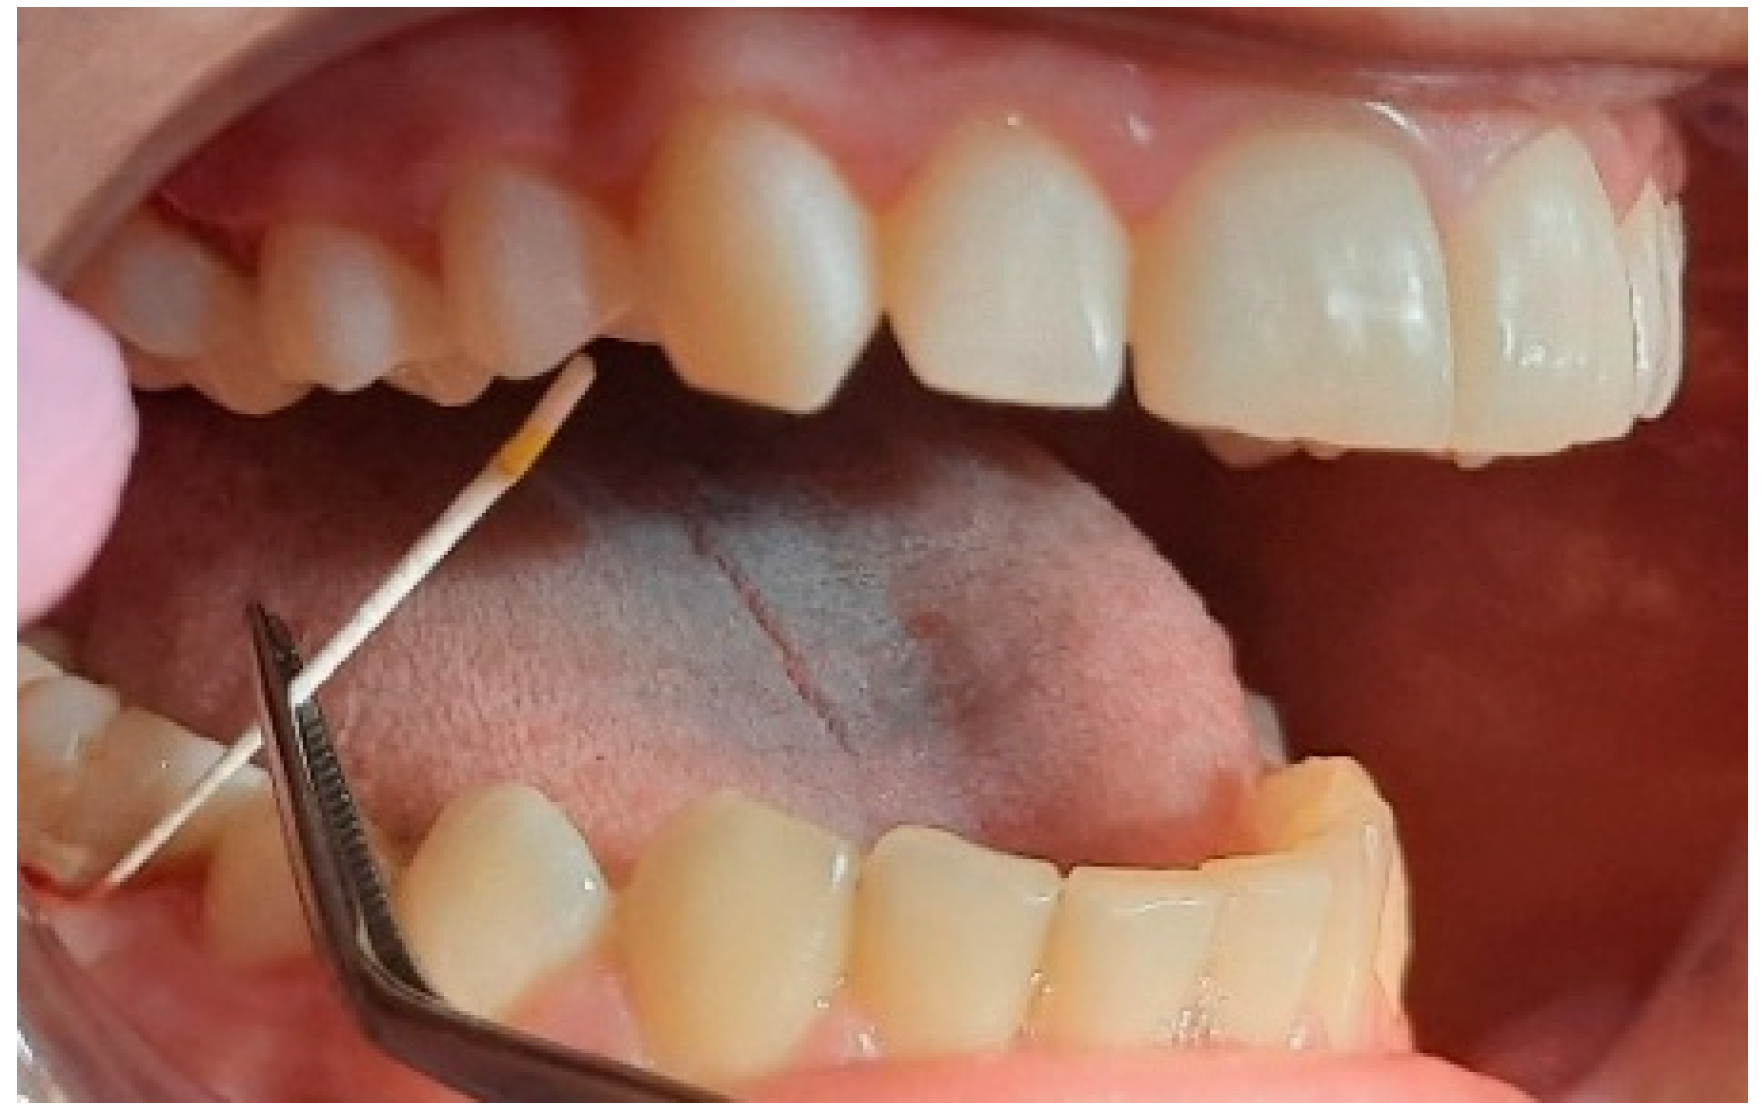

2.2. Clinical Examinations

3.2. Analysis of Clinical Data